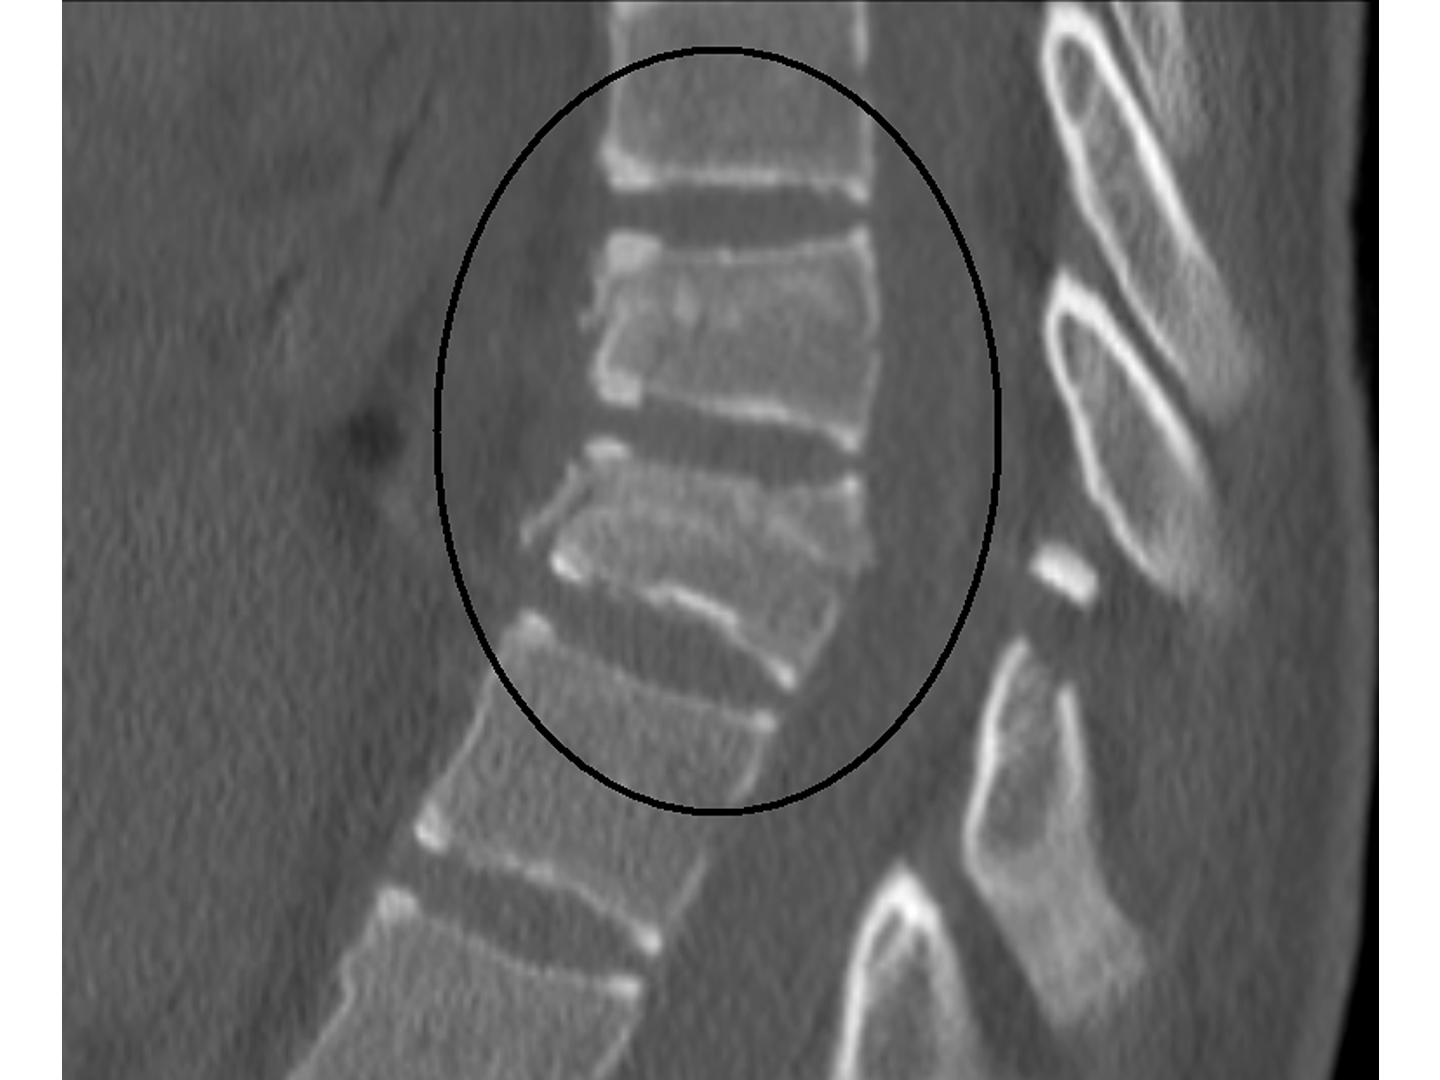

Sie ist die häufigste Wirbelkörperfraktur der oberen HWS. Sie entsteht meist durch einen Sturz auf den Kopf- oder Halsbereich. Siehe [[Abb. 788]]